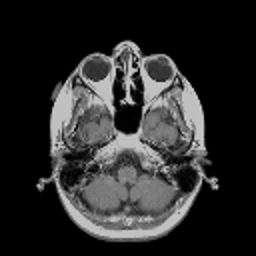

VII-C Experiments with real-life data

Reconstruction of real-life MRI images has been the next step in our comparative study. To this end, the data set of [19] have been used herein. The data were obtained at the University Hospital of Ghent and it is publicly available at http://telin.ugent.be/~sanja/Sanja_files/Software/MRIprogram.zip. The data contains a sagittal and an axial scan of a human brain, which are shown in Fig. 10 and Fig. 11, respectively.

The reconstruction results obtained for each of the tested images using the proposed and reference methods are shown in Subplots (b)-(f) of Fig. 10 and Fig. 11, respectively. From these figures, it can be seen that the proposed algorithms result in higher-contrast reconstructions of better visual clarity as compared to the reference approaches. The difference is particularly evident for the case of Fig. 11, where the proposed algorithms result in less noisy images, while exhibiting higher effective resolution and contrast.

Figure 10: (a) Sagittal MRI scan; (b)-(f) Reconstruction results obtained using TVDN, WDN, GNLM, NLMS and NLMR, respectively.

Refer to caption

Figure 11: (a) Axial MRI scan; (b)-(f) Reconstruction results obtained using TVDN, WDN, GNLM, NLMS and NLMR, respectively.